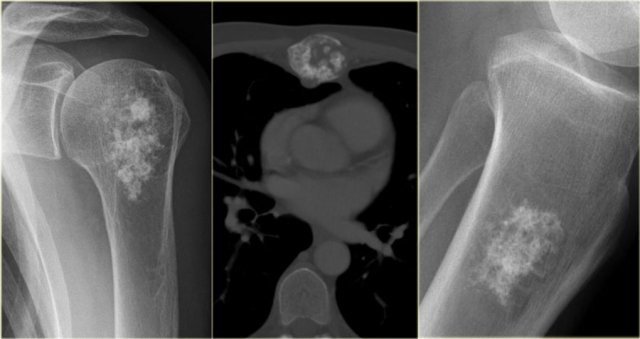

Here a lesion consisting of rings-and-arcs calcifications in the proximal humerus.

The differential diagnosis is enchondroma or low grade chondrosarcoma.

The CT shows the calcifications with subtle endosteal thinning of the cortical bone (arrows).

Final diagnosis: low grade chondrosarcoma.

Chondrosarcoma (13)

Here a patient with a lesion in the proximal humerus with typical popcorn calcification.

The most likely diagnosis is enchondroma, however progression to a low-grade chondrosarcoma cannot be excluded based on the plain radiograph alone.

There is increased activity on the nuclear bone scan, which is more in favor of the diagnosis of a chondrosarcoma.

This proved to be a low-grade chondrosarcoma.